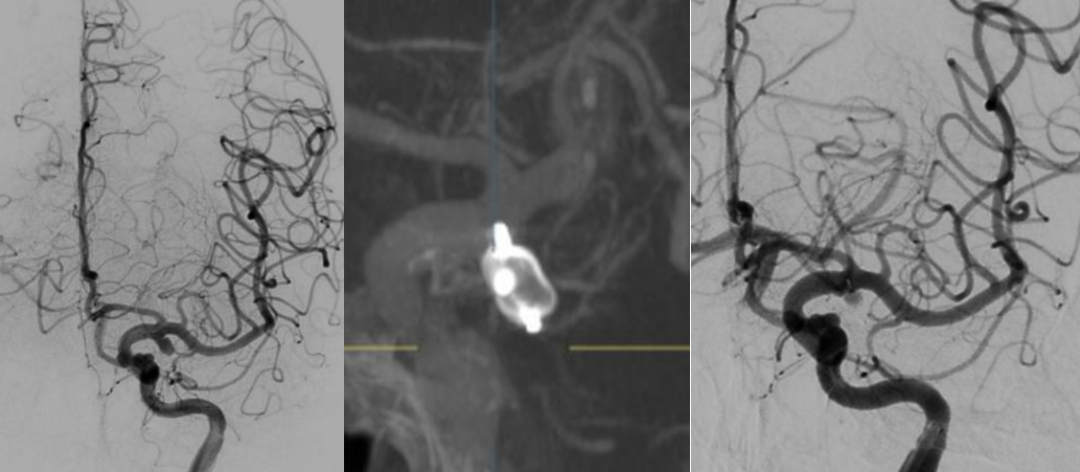

“时间就是生命,必须立即手术!”神经外科专家团队当机立断,提出立即实施脑血管造影,同步准备动脉瘤栓塞手术,术后再行脑室外引流的治疗方案。在征得家属同意后,医院迅速启动急诊手术绿色通道,联动麻醉科、介入导管室等多个科室组建专项救治团队。脑血管造影结果精准定位为左颈内动脉后交通段宽颈动脉瘤,综合考量患者年龄、身体状况等因素,家属最终选择创伤更小、无需二次双抗的WEB扰流装置置入术。

手术团队争分夺秒,顺利完成WEB扰流装置置入术后,紧接着实施双侧脑室外引流+颅内压监测术,通过精准调控脑脊液释放速度和降压药用量,为患者筑牢生命防线。然而救治过程并非一帆风顺,术后当晚,李大叔突发右侧瞳孔散大,医护人员第一时间复查CT,排除脑积水和新增出血后,判断为脑血管痉挛所致。团队立即调整治疗方案,加强扩管、镇静治疗,至深夜11点,患者瞳孔恢复正常。为加速清除颅内积血,团队随后为其施行腰大池引流管置入,通过“三管齐下”的精准干预,全力保障患者脑部功能。

▲术前后造影